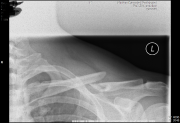

unschöne sache

soviel metall hab ich schon lange nicht mehr gesehn^^ wie schafft man sowas?

Und ich hab neulich die Röntgenbilder von einem Freund gesehen - der hatte noch mehr eisen in seiner Schulter stecken...